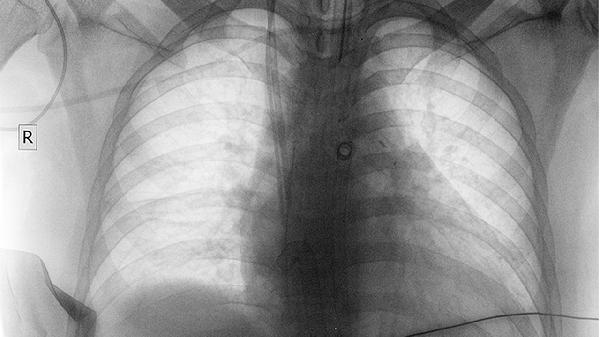

1、低剂量CT检查

相比胸片,低剂量CT能发现更小的肺部结节,是国际公认的肺癌筛查金标准。